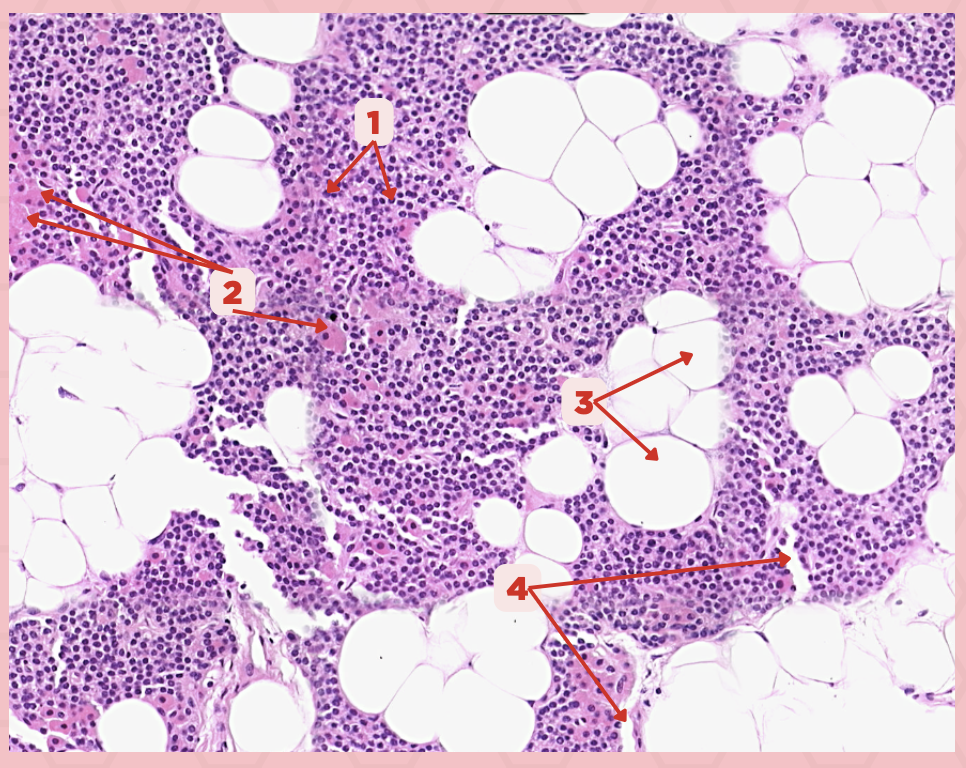

Parathyroid

Identify the specimen.

Chief Cells

Identify the specimen labeled as 1.

Oxyphil Cells

Identify the specimen labeled as 2.

Adipocytes

Identify the specimen labeled as 3.

Capillaries

Identify the specimen labeled as 4.

Newborns

Pointer #2 is hardly present in the parathyroid glands of _____.

Parathyroid

Identify the specimen.